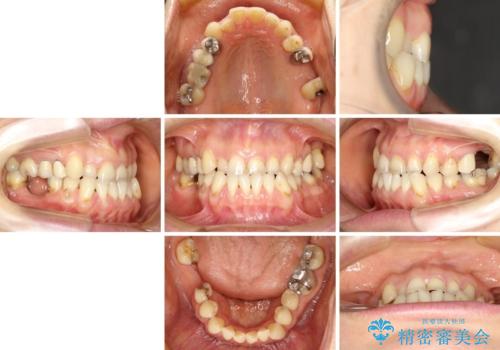

反対咬合や欠損を治療したい インビザライン矯正とオールセラミックブリッジ

- 虫歯治療がうまく進まないとのことで来院された患者様です。

虫歯治療や欠損補綴治療も必要でしたが、前歯が反対咬合であったので、セラミッククラウンやブリッジによる治療と並行して矯正治療を提案しました。

仕事柄海外出張が多いとのことで、虫歯治療後にインビザラインにて矯正治療を行うこととしました。

海外出張にとどまらず海外赴任もあり、途中2度の妊娠もあったため、治療には非常に長い期間を要することとなりました。